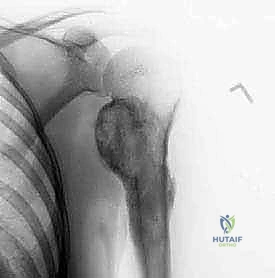

Our patient presents with pain, restricted range of motion, and a mass in the proximal humerus. Imaging confirms a low-grade sarcoma, specifically a chondrosarcoma, which has been pretreated with neoadjuvant chemotherapy, showing a good response. This intra-articular resection is indicated for such benign but aggressive tumors or well-responded sarcomas, where preservation of the abductor mechanism is feasible.

* Plain Radiographs (AP, lateral, axillary views): These were our initial diagnostic tools, providing crucial clues to the nature of the neoplasm – note the bone expansion and cortical thickening characteristic of chondrosarcoma.

Figure 3: Preoperative AP and lateral radiographs of the proximal humerus showing a chondrosarcoma.